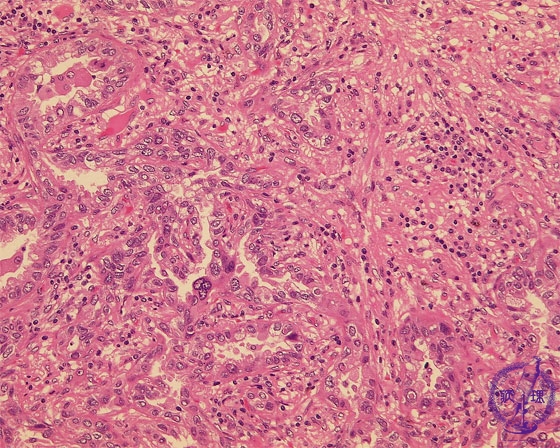

- ★(17)Non-small cell lung carcinoma(adenocarcinoma)

Microscopic view (HE stain, high power view): Adenocarcinoma of lung. Centrally within the carcinoma, tumor cells form irregular tubules and proliferate by invasion. There is a predominantly lymphocytic infiltrate within the complex, intricate stroma.